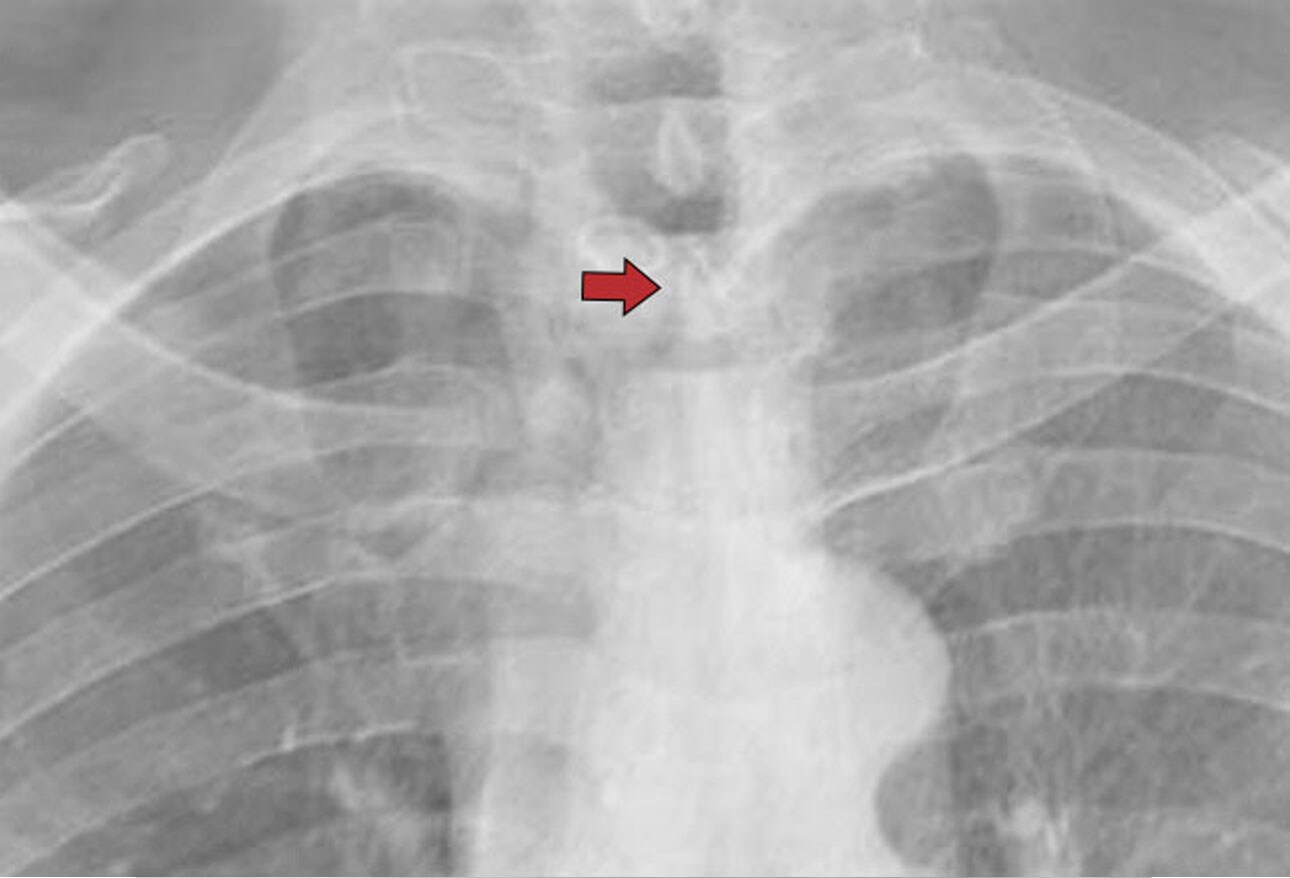

Chest radiograph is apparent for luminal narrowing of the trachea Tracheal Stenosis Cxr The goal of this study was to describe the characteristics and prognosis. In patients with chronic stricture,. In a patient with post traumatic tracheal stenosis (e), an axial ct image (e) of the proximal thoracic trachea. The trachea extends from the lower border of the larynx (2 cm below the vocal cords) to the carina, where it bifurcates into the.. Tracheal Stenosis Cxr.

Preoperative chest Xray shows tracheal stenosis. Download Scientific Tracheal Stenosis Cxr In a patient with post traumatic tracheal stenosis (e), an axial ct image (e) of the proximal thoracic trachea. The goal of this study was to describe the characteristics and prognosis. Ulceration of the mucosa and inflammation with granulation tissue formation produce the. Subglottic stenosis (sgs) and tracheal stenosis (ts) are characterized by a narrowing of the airways. In patients. Tracheal Stenosis Cxr.